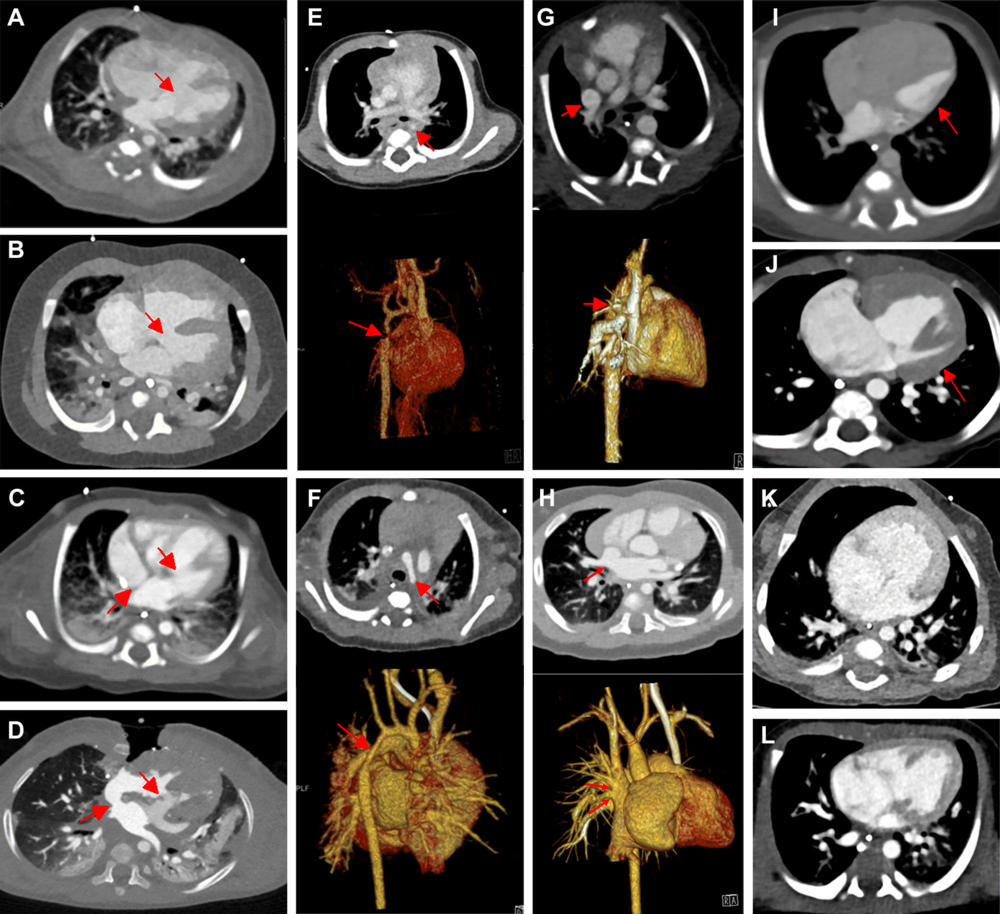

Figure 2. Contrast-enhanced axial dual-source CT (DSCT) versus contrast-enhanced axial photon-counting CT (PCCT) interindividual comparisons in typical congenital heart defects. (A) DSCT image in a 15-day-old male infant suspected at sonography of having ventricular septum defect (arrow). (B) PCCT image in a 155-day-old male infant suspected at sonography of having ventricular septum defect (arrow). (C) DSCT image in a 25-day-old male infant suspected at sonography of having atrioventricular septum defect (arrows). (D) PCCT image in a 355-day-old male infant suspected at sonography of having atrioventricular septum defect (arrows). (E) Contrast-enhanced and three-dimensional (3D) DSCT images in a 128-day-old male infant suspected at sonography of having aortic isthmus stenosis (arrows). (F) Contrast-enhanced and 3D PCCT images in a 16-day-old male infant suspected at sonography of having hypoplastic aortic arch (arrows). (G) Contrast-enhanced and 3D DSCT images in a 63-day-old male infant suspected at sonography of having partial anomalous pulmonary venous connection (arrows). (H) Contrast-enhanced and 3D PCCT images in a 174-day-old male infant suspected at sonography of having partial anomalous pulmonary venous connection (arrows). (I) DSCT image in a 2-day-old male newborn with hypoplastic left heart syndrome (arrow). (J) PCCT image in a 149-day-old male infant with hypoplastic left heart syndrome (arrow). (K) DSCT image in a 10-day-old male newborn with double outlet right ventricle. (L) PCCT image in a 7-day-old female newborn with double outlet right ventricle.